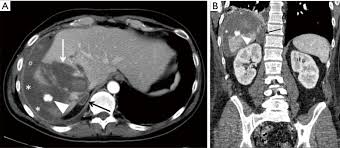

Optimal Diagnosis Of Adrenal Masses Sciencedirect

Optimal Diagnosis Of Adrenal Masses Sciencedirect from ars.els-cdn.com

The adrenal gland is involved by a range of neoplasms, including primary and metastatic malignant tumors; Usually, it is a small round mass. Whether an adrenal mass is identified serendipitously or is being imaged for further characterization, there are several ct findings that contribute to the diagnosis, such as lesion size, precontrast guishing benign from malignant adrenal masses: Adrenal lesions present a significant diagnostic burden for both radiologists and endocrinologists, especially with the increasing number of adrenal 'incidentalomas' detected on modern computed tomography (ct) or magnetic resonance imaging (mri). Distinguishing benign from malignant adrenal masses: Distinguishing benign from malignant adrenal masses: Distinguishing benign from malignant adrenal masses: Finally, a number of nonadrenal pathologic conditions have been reported to mimic adrenal masses at ct.

Ct image of another adrenal mass mainly composed of macroscopic fat. A key objective is the reliable distinction of. Prior imaging if available) and cancer history. Population covered by the guidance. Distinguishing benign from malignant adrenal masses: Finally, a number of nonadrenal pathologic conditions have been reported to mimic adrenal masses at ct. Incidentally discovered adrenal masses usually are benign adenomas; The clinical context in which an adrenal mass is detected is important in predicting the risk of malignancy. Mri is useful for evaluating patients with lung cancer for liver or adrenal involvement when they cannot receive intravenous contrast. Adrenal masses <1 cm do not require further investigation. Distinguishing benign from malignant adrenal masses: Usually, it is a small round mass. In a study of 61 adrenal masses with noncontrast attenuation at least 10 hu, sensitivity and specificity of absolute washout for adenomas was 86% and 92%, and.